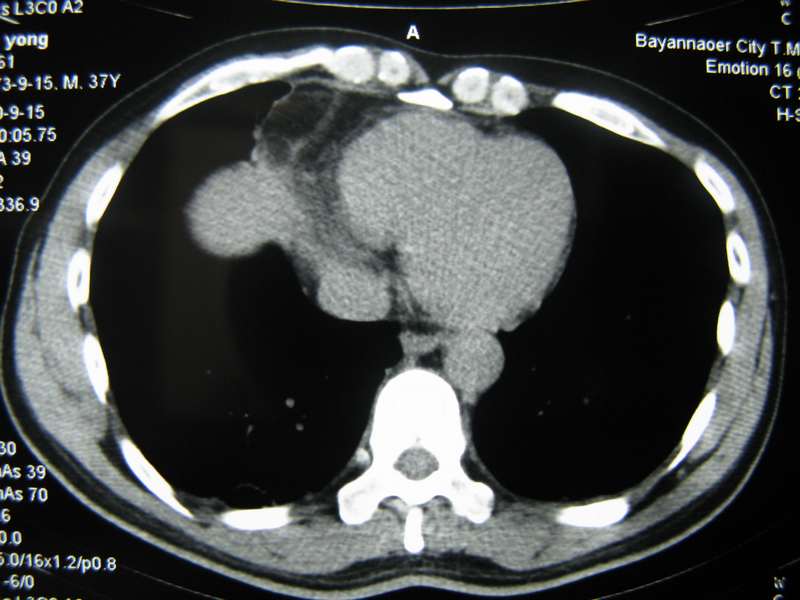

男,37岁,主述胸疼厉害,无咳嗽,无发热,血象也不高,病灶内ct值脂肪密度,右侧胸腔内少量积液,同道们考虑什么?谢谢!

两肺下叶基底段纤维灶,右肺下叶基底背侧相应胸膜肥厚,右肺中叶内侧段部分不张。前中下纵隔团块状脂肪影,随访除外胸腺脂肪瘤。

不除外膈疝。